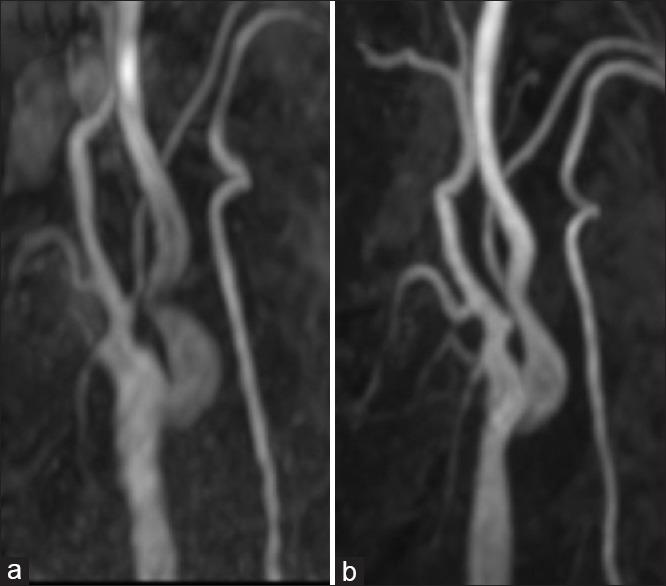

A 73-year-old female was referred to our department with fugacious amaurosis and transient sensory disturbance in the left upper limb due to moderate stenosis of the right ICA that was treated by CEA 28 days after admission. However, postoperative angiography and carotid Doppler revealed a kinked ICA with a high-flow velocity that was not present intraoperatively. After 3 months, she had suffered transient ischemic attacks that were refractory to medical treatment, so we performed CAS to prevent future events. The kinked ICA was immediately resolved by stenting and there was no restenosis at a follow-up angiogram 19 months later.

This case shows that CAS could be a potential therapeutic option for the management of symptomatic kinking stenosis of the ICA after CEA.